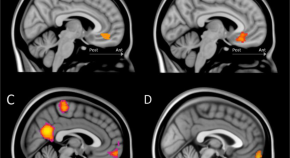

Current models of human fear learning processes emphasize a primary contribution of the ventromedial prefrontal cortex (vmPFC) to fear inhibition (i.e., fear extinction). Here, we discuss crucial findings from recent brain imaging studies that highlight the role of vmPFC and its subregions in how fear is acquired (i.e., fear conditioning).